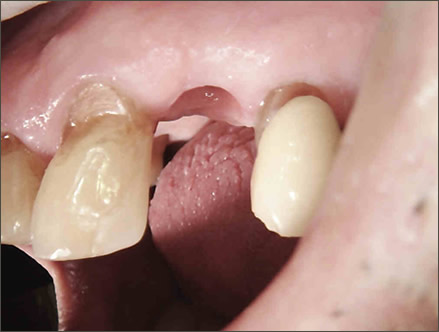

IMPLANTS FOR SINGLE & MULTIPLE MISSING TEETH

Dental implants are the best-known treatment to replace single or multiple missing teeth because they feel and behave just like natural teeth. After a while you won’t be able to tell the difference – even forgetting that they are there.

The procedure to place implants and replace a missing tooth or multiple teeth is straightforward as there is little need to treat surrounding teeth. Once a crown is placed over the implant it will appear indistinguishable from the natural teeth.